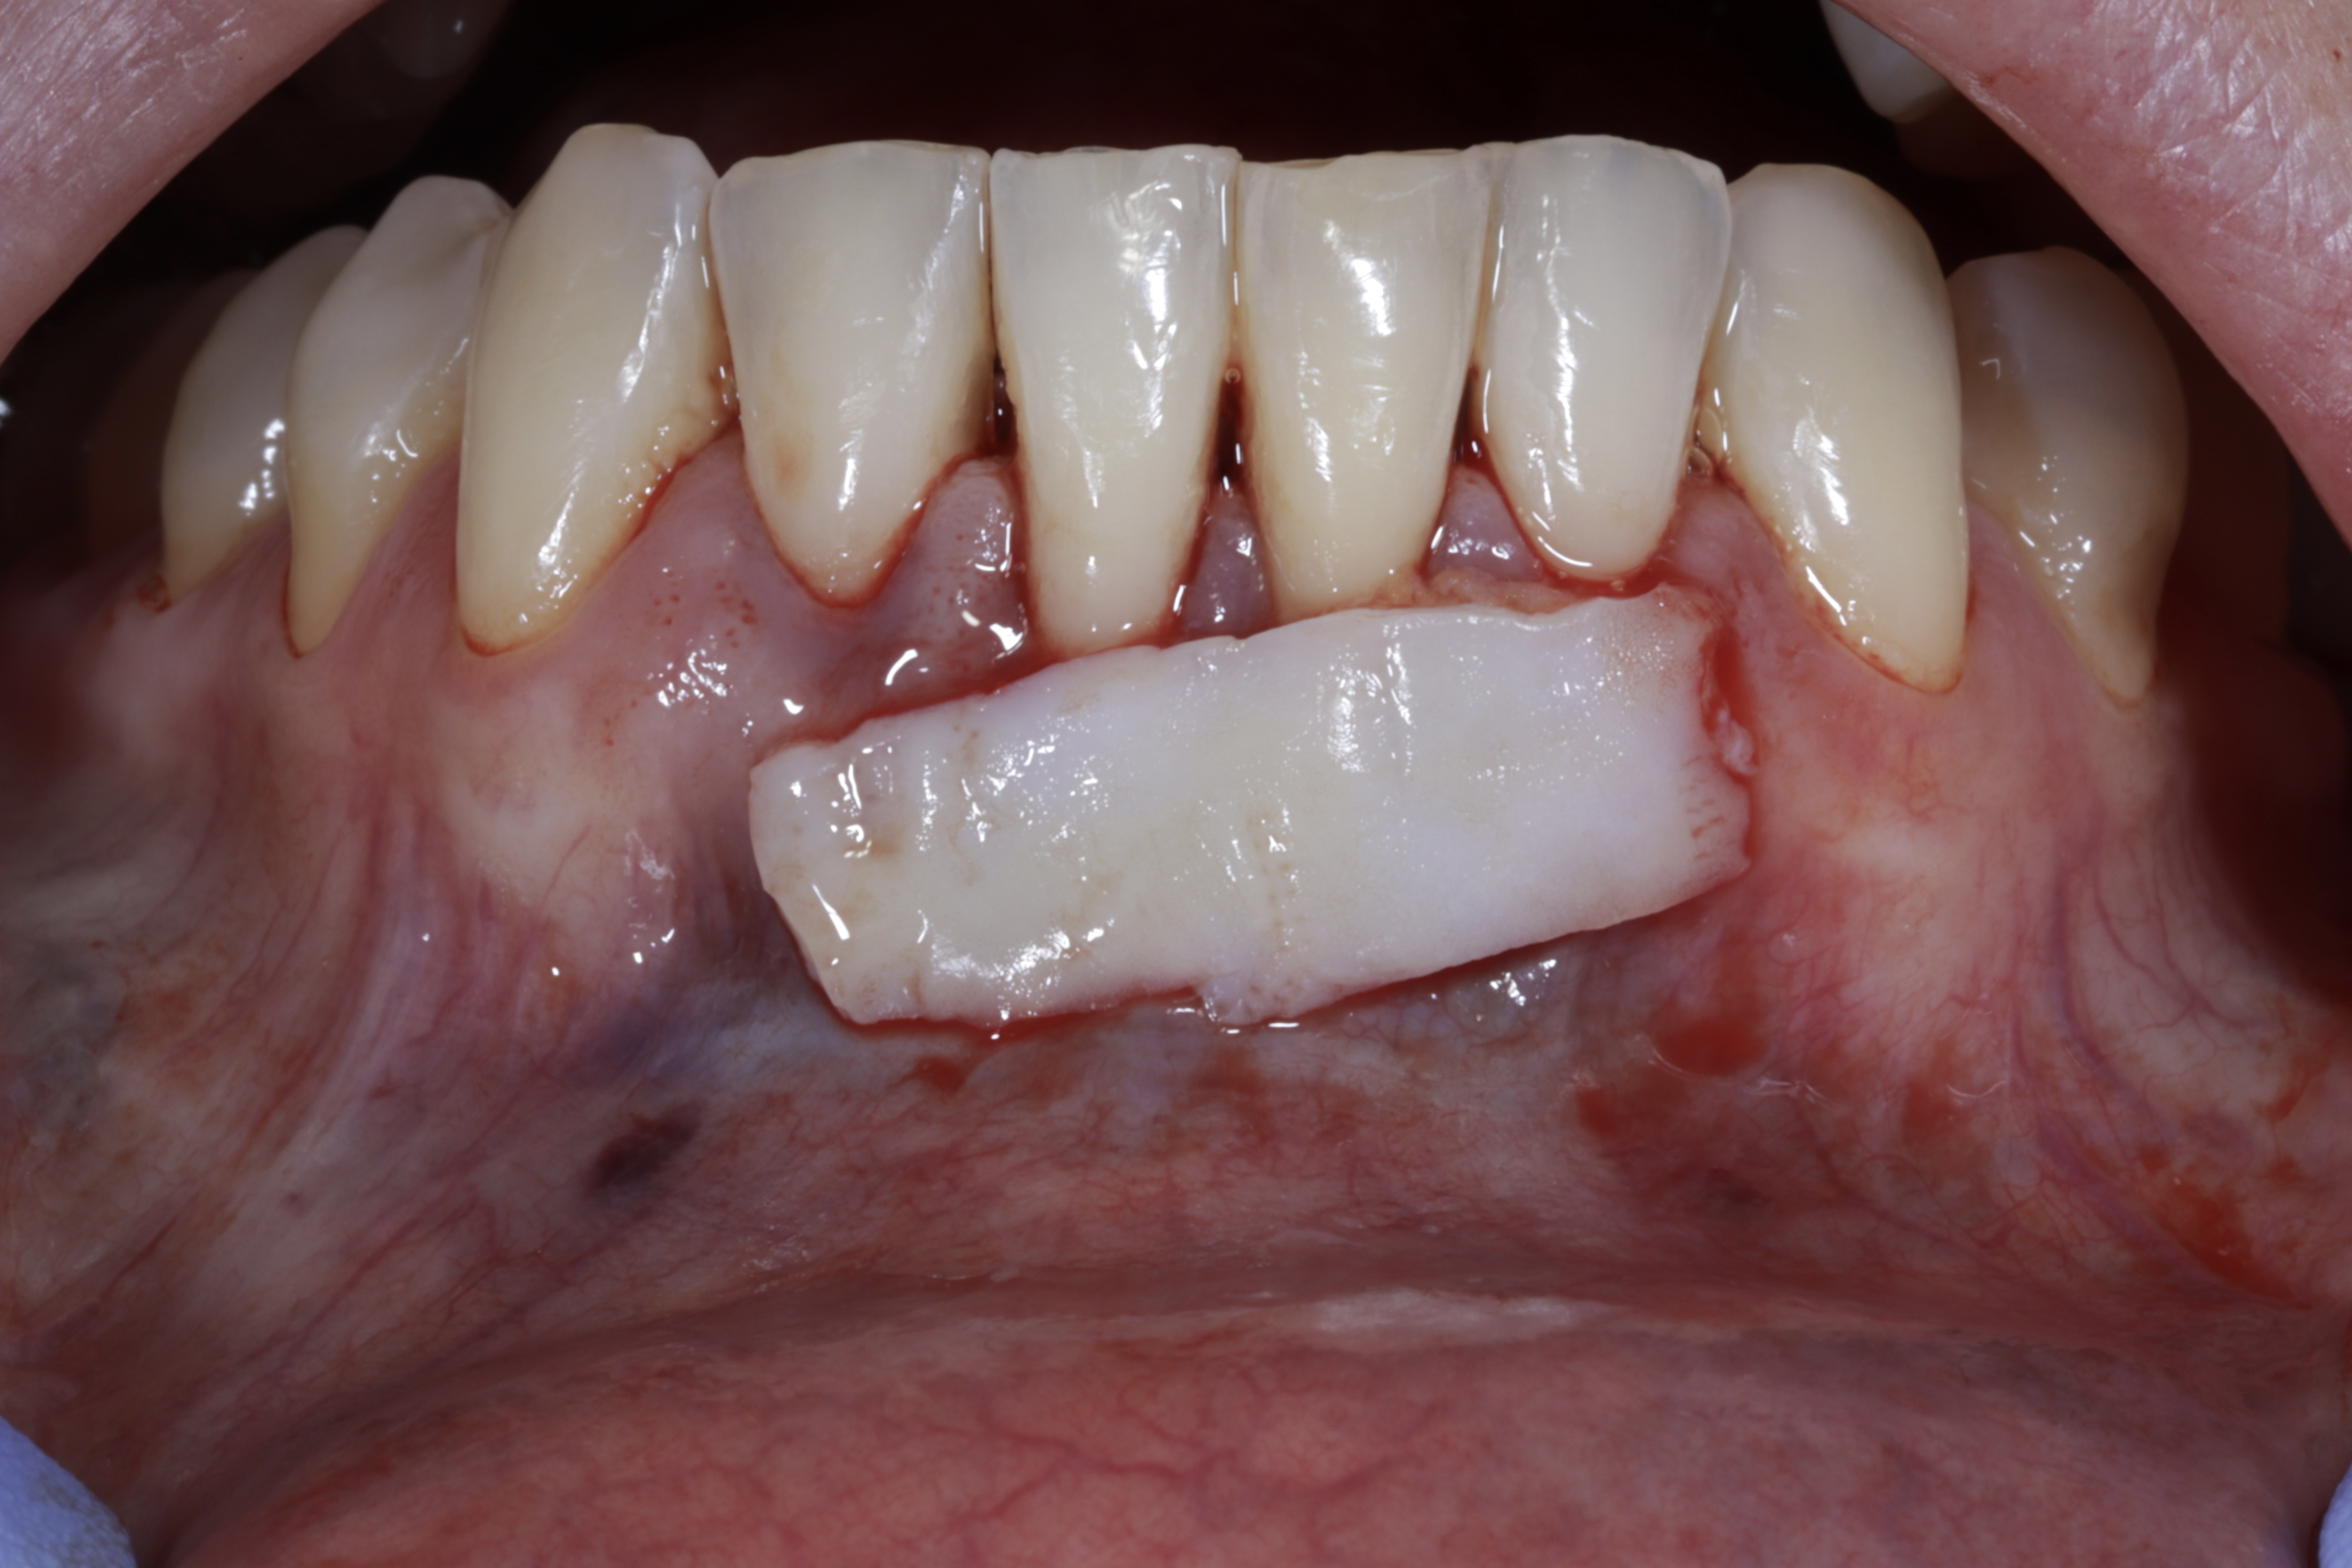

Se realizará todo el procedimiento con un microscopio operatorio, lo que permite al alumno ver toda la cirugía en directo en una pantalla en la sala de cirugía.

Los dientes remanentes del maxilar superior serán extraidos, se colocarán 5 implantes inmediatos flapless y 3 más con fresas de

Toda la cirugía se llevará a cabo con un microscopio operatorio y el paciente estará bajo sedación consciente.

Los alumnos pueden ver la cirugía en una pantalla, previa explicación del caso y posteriores explicaciónes durante la carga inmediata.

Ya se han realizado la extracción de los dientes 12, 11, 21, 22 para garantizar el cierre de tejidos blandos. El día de la cirugía, el alumno verá todo el procedimiento en una pantalla en directo en la sala de cirugía, ya que todo será realizado con un microscopio operatorio.

Se extraerán los